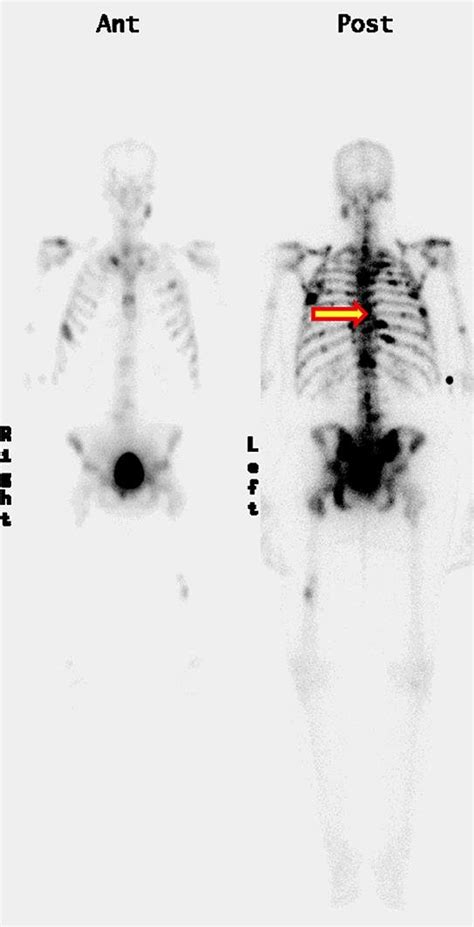

Now, let’s talk about why bone scans are so darn important when it comes to detecting bone metastasis on bone scan . You might be thinking, “Can’t they just do an X-ray?” Well, X-rays are great for showing major breaks or changes in bone density, but they often can’t pick up the subtle changes that happen in the very early stages of bone metastasis. This is where the bone scan shines! Think of a bone scan as a super-sensitive detector. It uses a small amount of a radioactive tracer, usually Technetium-99m MDP. This tracer travels through your bloodstream and is absorbed by bones. Bone is constantly remodeling itself – breaking down old bone and building new bone. When cancer cells invade the bone, they trigger an accelerated process of bone breakdown and rebuilding in that specific area. The radioactive tracer is taken up more readily by these areas of increased bone activity. So, the ‘hot spots’ that show up on the scan indicate areas where there’s more metabolic activity – and in the context of cancer, this often means metastasis. It allows doctors to see the entire skeleton at once, catching any spots that might be missed by other imaging methods. This comprehensive view is absolutely vital for staging the cancer and determining the best course of treatment. Without this detailed map provided by the bone metastasis on bone scan , doctors might be working with incomplete information, which could lead to less effective treatment strategies. So, yeah, bone scans are a pretty big deal in the world of cancer diagnostics, especially when dealing with potential spread to the bones.

This is the part where we talk about interpreting the results of your bone metastasis on bone scan . It’s a bit like being a detective, piecing together clues from the images. The radiologist, a doctor who specializes in reading medical images, will carefully examine the scan. They’re looking for ‘hot spots’ – areas that have taken up more of the radioactive tracer than the surrounding bone. These hot spots can indicate areas of increased bone activity. Now, here’s a crucial point: not all hot spots mean cancer . There are other conditions that can cause increased bone activity, such as arthritis, infections, recent fractures, or areas where bone has been surgically altered. That’s why the radiologist doesn’t just look at the scan in isolation. They’ll consider your medical history, any symptoms you’re experiencing, and results from other tests, like biopsies or other imaging studies. If the hot spots are in locations consistent with cancer spread, and if there are multiple such spots throughout the skeleton, it strongly suggests bone metastasis. The report from the radiologist will detail the location, number, and appearance of any suspicious areas. Your oncologist (your cancer doctor) will then review this report along with all your other medical information to make a diagnosis and develop a treatment plan. It’s a collaborative effort, and understanding these results is a key part of your journey. Don’t hesitate to ask your doctor questions about what the bone metastasis on bone scan shows – it’s your body, and you have the right to understand what’s going on.